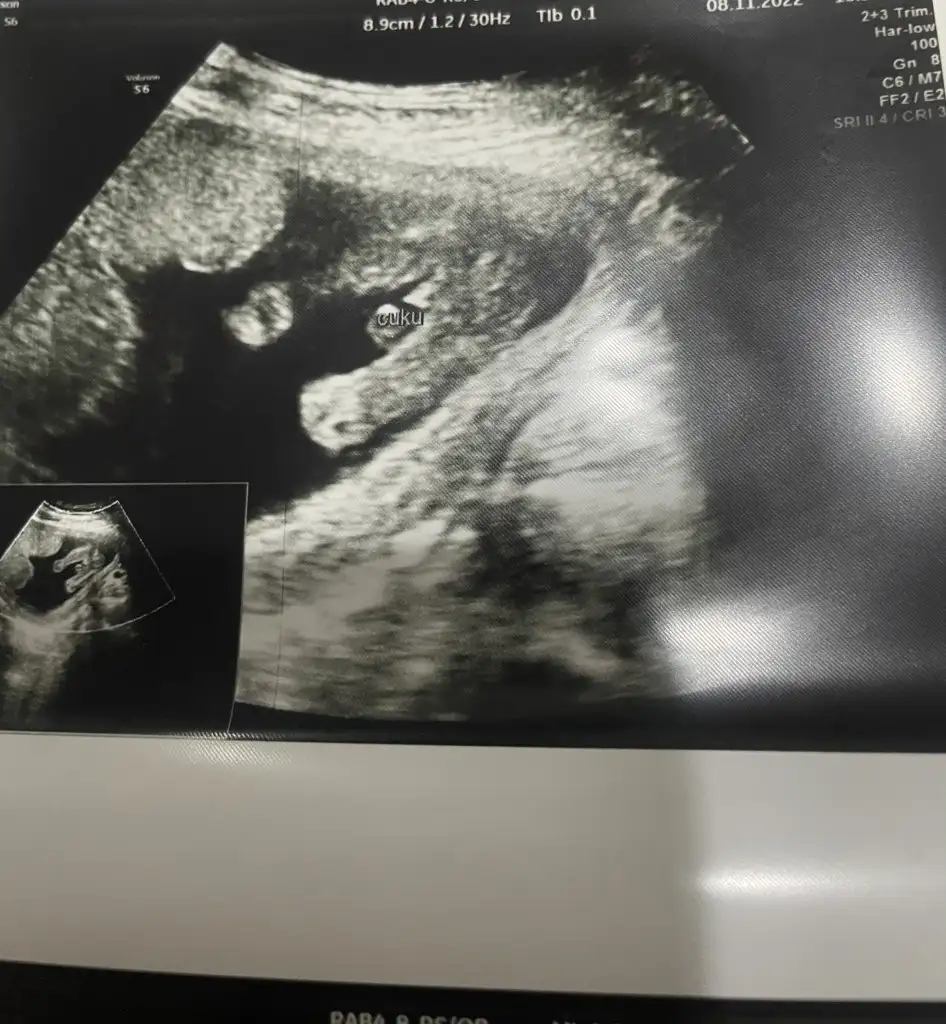

16. Hafta görüntüsü bu detaylı ultrasonu beklemeli miyim?Kızlar merhaba benimde doğumum 25 nisan olacak inşallah. 12. Haftada kız demişti doktor ama dün kontrole gittik erkek dedi biraz hayallerim yıkıldı değişir mi sizce başına böyle birşey gelene var mı Eki Görüntüle 3158572